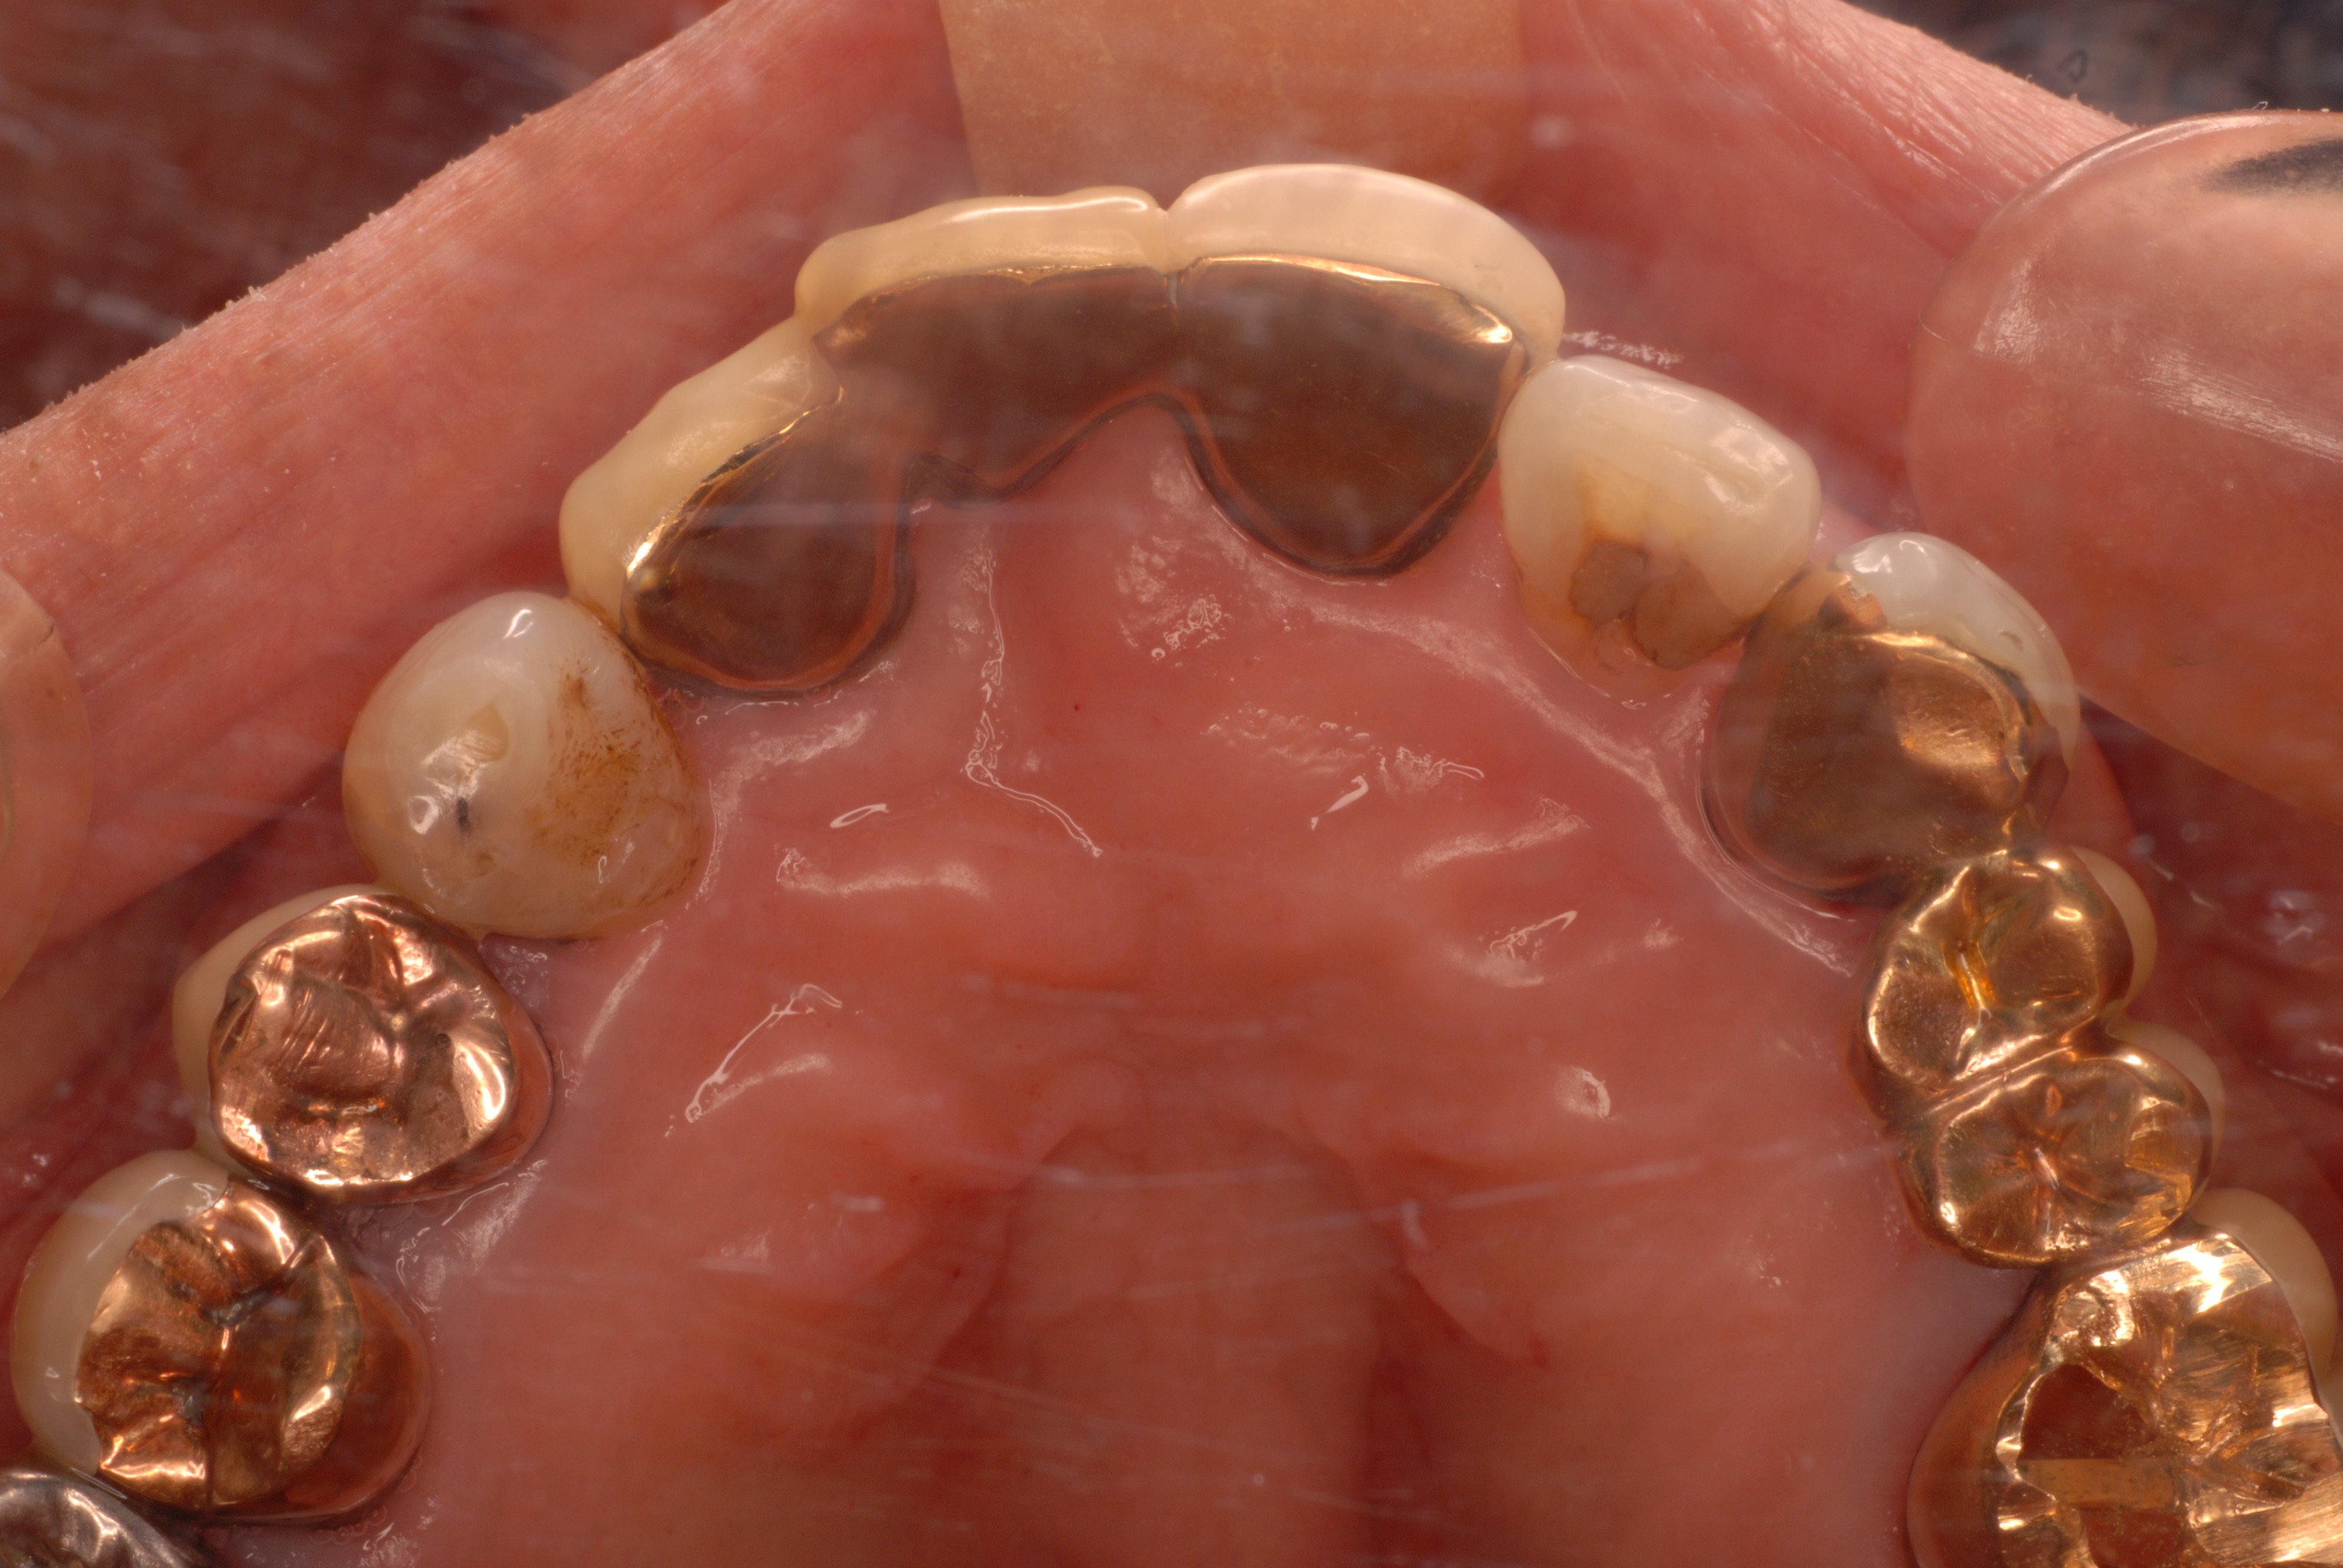

お口の中には高価なセトモノや金歯が多いのですが、

残念ながら健康になったわけではないのです。

分岐部の歯周病を見逃した為に頬が腫れあがり診察の結果、

歯の歯折か重症の分岐部の歯周病と判断した患者さんです。

検査の為に歯茎を開き少し悪いところを取って様子を見ていたのですが、又激痛が走りその為応急処置として東洋医学で対処しました。

ですが、根本的に悪いところを取らなくては再発するだけでなく歯そのものが駄目になる事をお話しして納得してもらい、セラミックを外しその後重症の分岐部の歯周病と判断して歯の一部分と悪い病気の歯肉をえぐりとったその後1週間後の写真です。

DSC_0012右上の奥から2番目の歯が問題の歯です。

DSC_0014

セトモノが入っていますが、だからと言って健康になったわけではないのです。切り取った歯の残りと切り取り後が痛々しいですね。